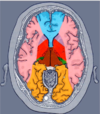

Lesion cerebral por esta arteria causa disfuncion de las siguientes estructuras

ACA

Lesion cerebral por esta arteria causa DISFUNCION DE:

ACM

Rama de la arteria carótida interna que produce sintomas como afecTACIÓN A CÁPSULA INTERNA que pueden involucrar radiaciones ópticas

ACOA

(Arteria coroidea anterior)